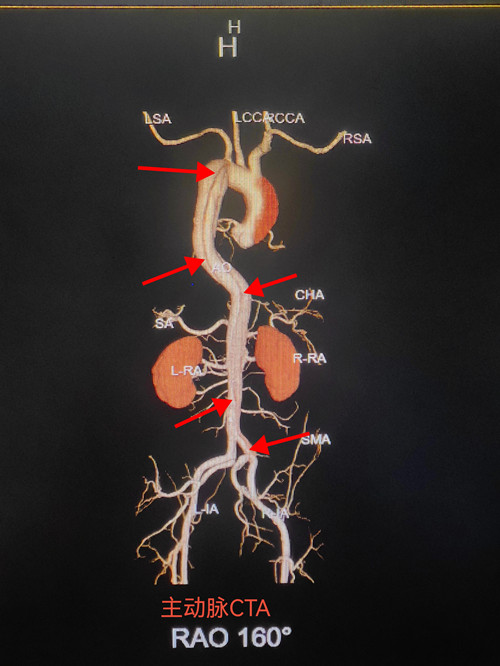

情况危急,患者随时可能因血管破裂猝死。戴炎栋不敢有丝毫迟疑,立即启动危急值报告程序,第一时间上报“夹层动脉瘤?”的可疑诊断,同时迅速与主管医生沟通,建议立即完善胸腹主动脉CT血管造影检查以明确诊断。在医院各科室的高效配合下,20时56分,患者顺利接受胸腹主动脉CTA检查。而检查结果让所有人都倒吸一口凉气:患者的夹层动脉瘤并非局限于腹部,而是从升主动脉一路延伸至髂动脉,贯穿整个胸腹盆腔,如此大范围的夹层动脉瘤在临床上极为少见,病情凶险程度远超预期。

“主动脉夹层的早期诊断是救治成功的关键,而CT平扫的隐蔽性给诊断带来了极大挑战。”戴炎栋医生介绍,常规CT平扫下,主动脉夹层可能仅表现为动脉增粗、钙化斑内移等不典型迹象,如同本次患者仅出现小片钙化斑内移,若稍不留意就可能漏诊,进而延误治疗时机。而胸腹主动脉CTA检查能清晰显示典型的“双腔征”,精准勾勒病变范围和累及部位,为疾病分型、手术方案制定提供可靠依据,其诊断灵敏度和准确率远高于常规CT平扫。